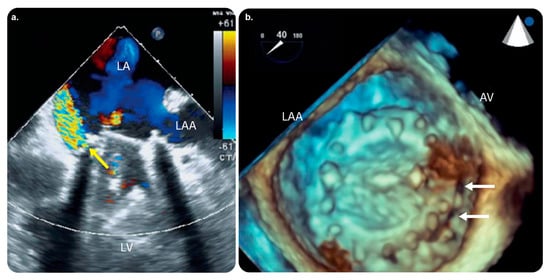

3.4.5. EchoNavigator

This live echo and X-ray fusion software aids interventionalists and surgeons who depend on live 3D transesophageal echocardiography (TEE) and live radiography for guidance during procedures for structural heart diseases. It imports live echo tissue information directly from fluoroscopic imaging and uses X-rays to automatically reflect the markers on soft tissue structures within the echo image. Furthermore, it automatically aligns with the C-arm orientation to interpret the images. The current version (3.0) is designed for use alongside one of the following X-ray systems: Azurion release 1.× to 2.× or Allura Xper release 7.6.× to 8.2.× (including the OR table series). EchoNavigator release 3.0 is also compatible with the following ultrasound systems: EPIQ CVxi Ultrasound devices (release 3.0) and later versions of x8-2t Echo probes [68,69,70,71] (Figure 12).

The available practical evidence is as follows.

Jone et al. [72] performed a prospective observational study to determine the usefulness of fused echocardiographic/X-ray fluoroscopic imaging (FEX; performed using EchoNavigator) in 25 pediatric patients with congenital heart disease (CHD) who underwent catheterization. They found that FEX reduced the fluoroscopy time and radiation exposure in arterial septal defect closure procedures.

Jungen et al. [73] performed a prospective observational study to investigate whether the automated real-time integration of 2D-/3D-TEE and fluoroscopy imaging in percutaneous left atrial appendage closure decreased radiation exposure to the patients and medical staff.

Ternacle et al. [74] concluded that EchoNavigator improved safety and facilitated communication between interventional team members.

Hadeed et al. [75] performed a prospective observational study on 51 pediatric patients with CHD who underwent TEE-guided catheterization. Image fusion was performed using EchoNavigator in all the cases. They concluded that EchoNavigator was a useful modality in terms of safety and aided interventionists in better recognizing the anatomy.